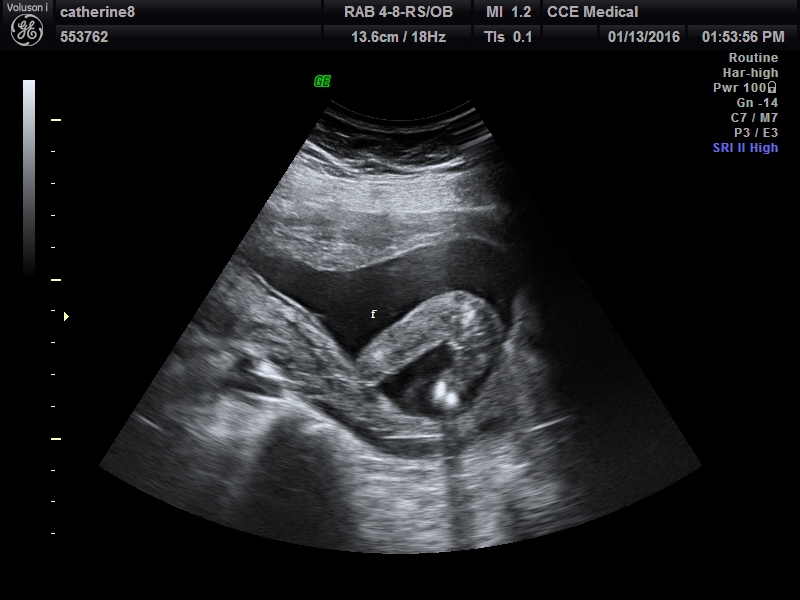

Dates were 12 weeks 2 days and baby was measuring 12 weeks 6 days. Saw the nub during the scan but didn't get a picture of what I saw!http://images.tapatalk-cdn.com/15/12...58a9a79d1c.jpg

Skull theory anyone?

I can see girly nub

too early but cute baby!

Too early but girly vibes!! Skull looks girly to me [emoji8][emoji175]!!

I'm not sure if the nub is forked or stacked. Do you have more pics?

No I don't. Just this one. The nub was so visible in the scan but didn't get a proper picture of it!!!

What did the nub look like to you? Flat or more boyish?

Claire it looked more girly to me but it could be just too early as well. Congrats on your little girl too!!